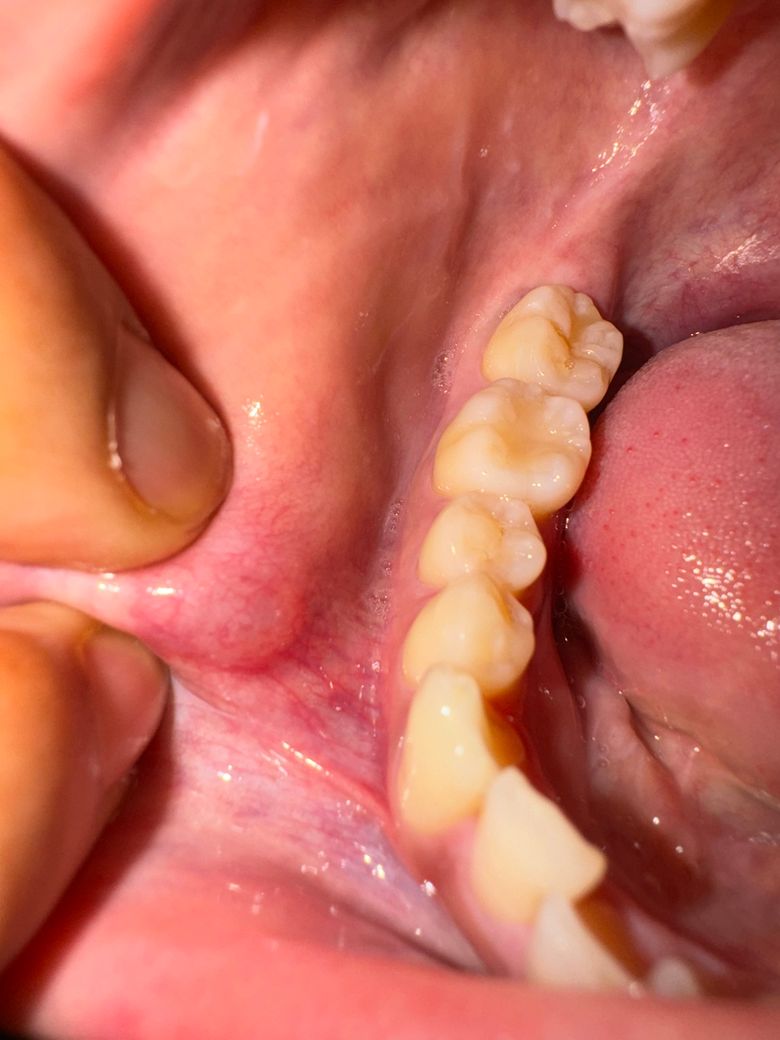

이렇게 변했다가 지금 생긴지 한달 반정도 되어가는데

• 2번 째 사진